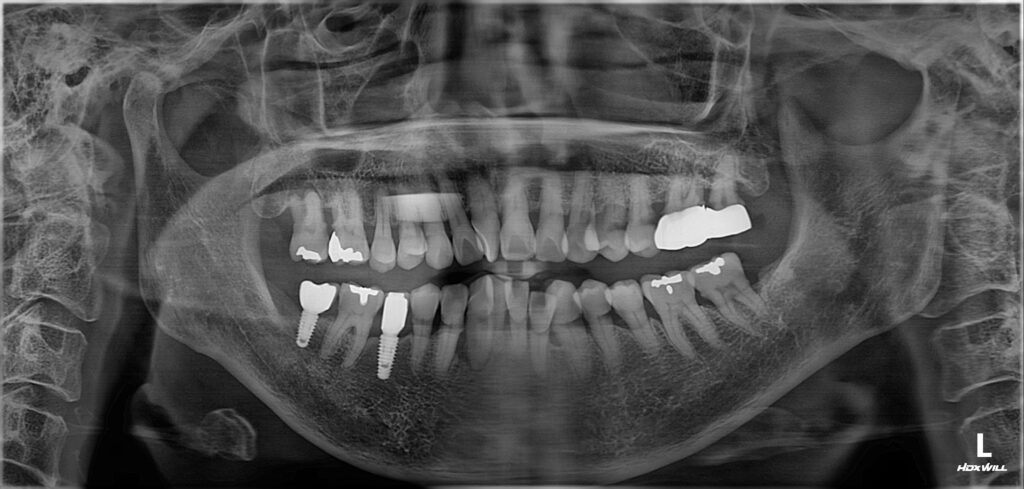

환자분께서는 70대 여성분으로

치아의 신경이 노출될 정도로 심하게

치경부가 패여 있는 상황이었는데요.

위쪽 작은 어금니 두개는 신경관이 보일 정도였지만

현재 증상이 없다고 하셔서 치수 복조 후 레진,

아래 송곳니는 신경치료 후 레진으로

수복할 수 있도록 계획하였습니다.